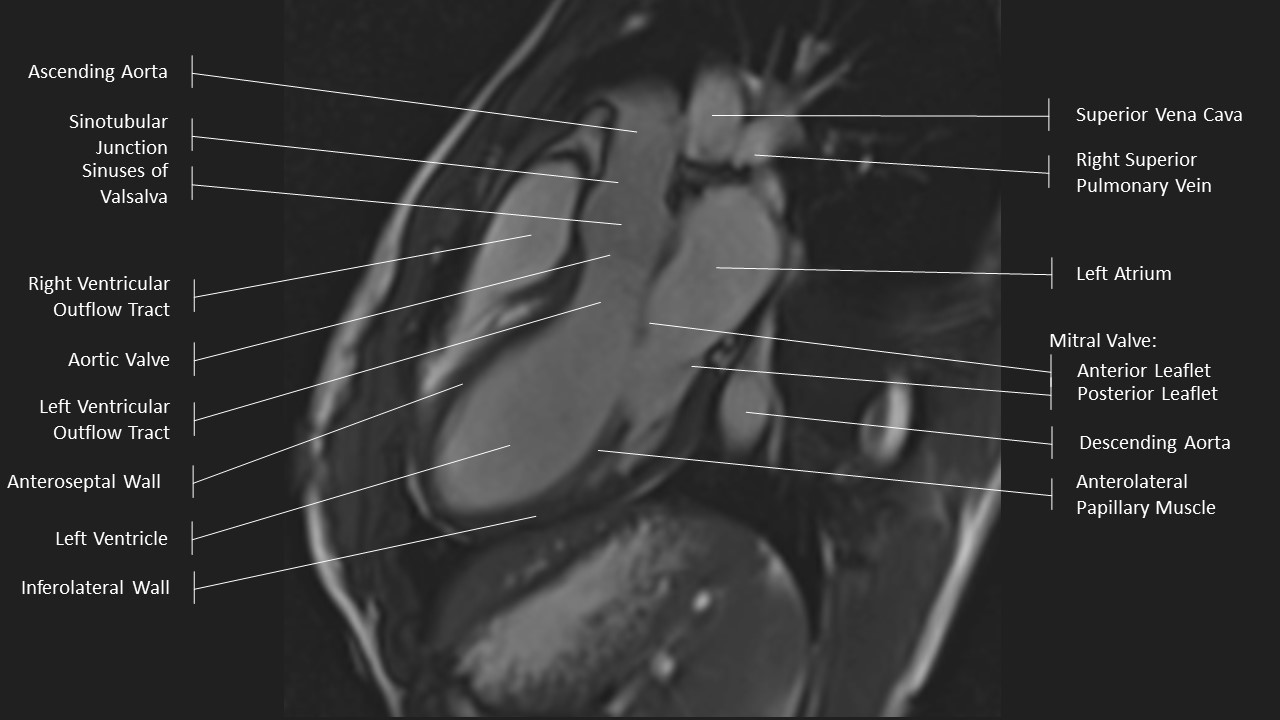

3 Chamber View